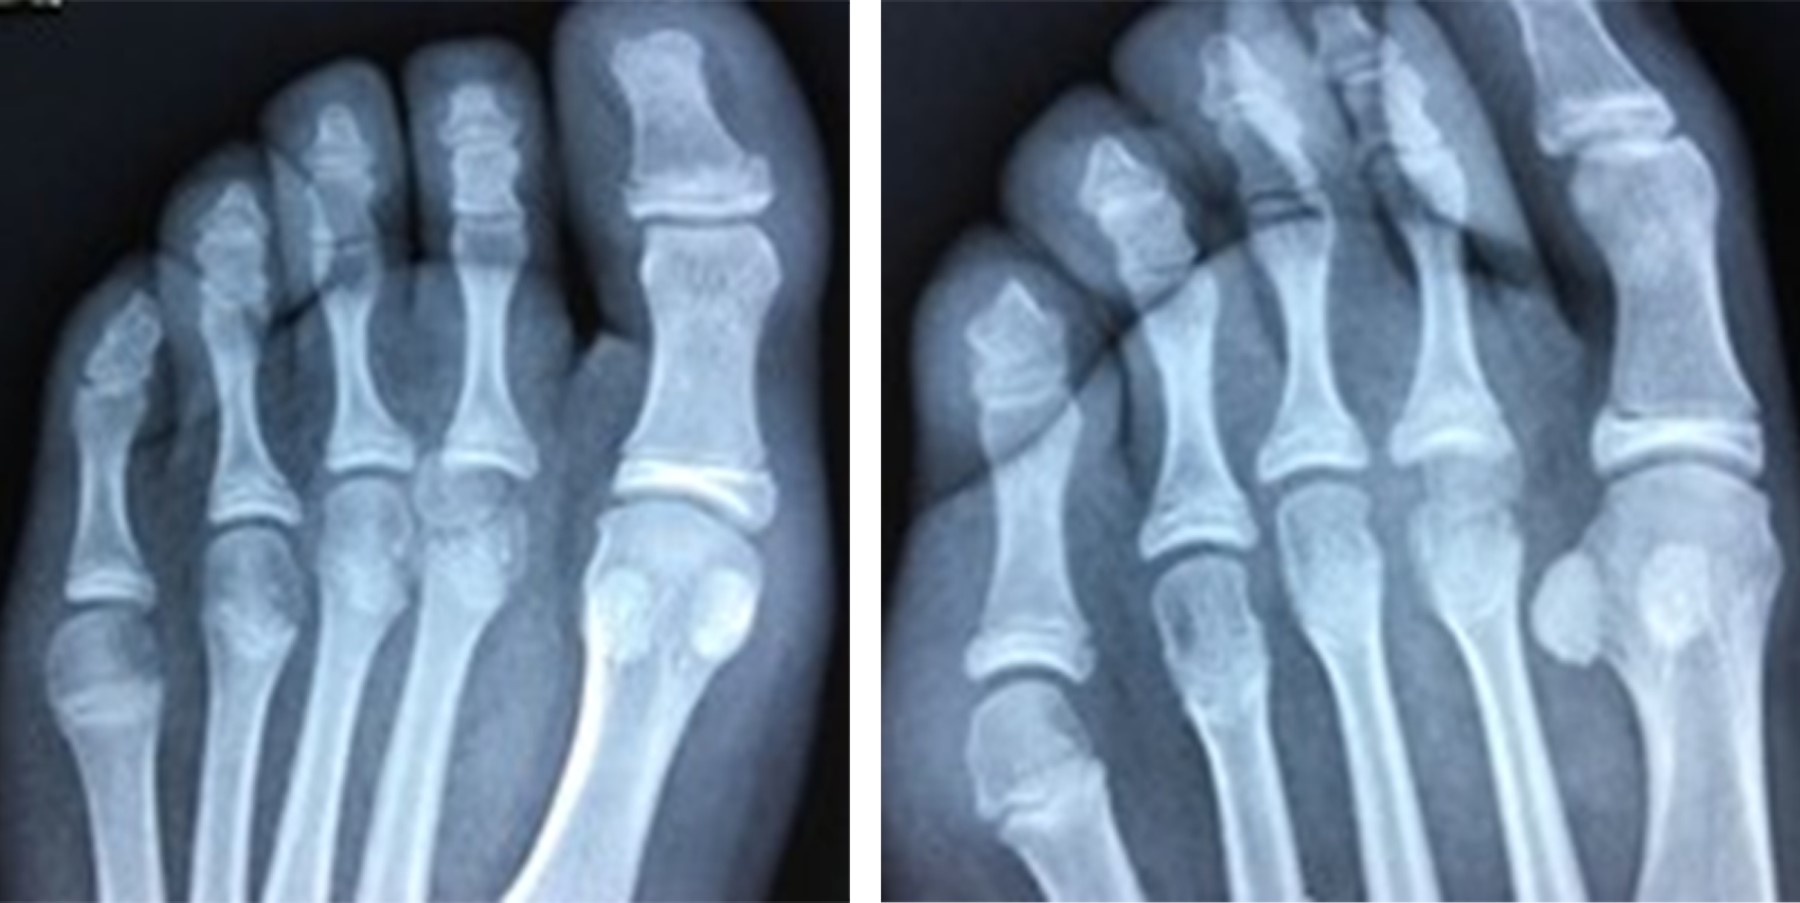

Se realizan radiografías anteroposterior (AP) y oblicua del pie (Figura 1). Se encuentra fractura epifisiaria desplazada de la cabeza del segundo metatarsiano.

Con previo consentimiento de los padres y la paciente, bajo anestesia local con lidocaína al 2% (3 cm3), se realiza reducción cerrada de la fractura epifisaria mediante tracción del segundo dedo y digitopresión en dirección plantar de la cabeza del metatarsiano. Se toman radiografías de control posterior al procedimiento; se encuentra reducción anatómica de la fractura (Figura 2). Se colocó zapato postquirúrgico por cuatro semanas y se reincorporó a actividades de la vida diaria dos meses posteriores a la fractura. Se realizó seguimiento clínico y radiológico de forma esporádica sin complicaciones en su evolución, se anexa radiografía a 36 meses de evolución (Figura 3).

Figura 1

Figura 2